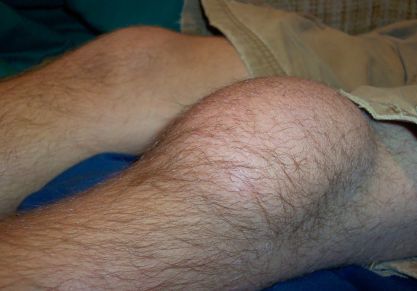

Супрапателлярный бурсит коленного сустава — симптомы и методы лечения

Cупрапателлярный бурсита коленного сустава, в чем его особенность? Способы диагностики и лечения. Медикаментозная терапия.

• Бурсит. Он считается достаточно неприятным заболеванием, которое характеризуется появлением воспалительного процесса в суставной сумке. При этом внутри полости сочленения накапливается экссудат.